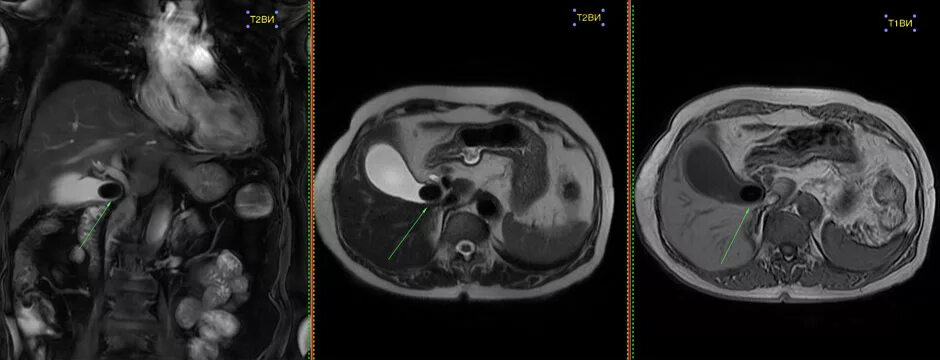

Камни в желчном мрт